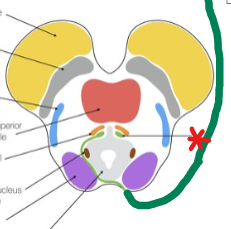

Superior Colliculus

A structure in the midbrain that is involved in visual processing and initiates eye movements

Edinger-Westphal Nucleus (EW)

A structure in the midbrain responsible for pupil constriction and lens accommodation.

Oculomotor Nucleus

A structure in the midbrain responsible for control of the motor functions of the oculomotor nerve.

Trochlear Nucleus

A structure in the midbrain responsible for the control of motor functions of the trochlear nerve.

Abducens Nucleus

A structure in the midbrain responsible for the control of motor functions of the abducens nerve.